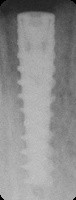

NobelActive Internal

Body Shape

Midbody groovesTapered apexTapered body

Thread Design

MicrothreadsSquare threadsThreadedV-shaped threads

Additional Features

Apical groovesFlat apeximplantStraight flange